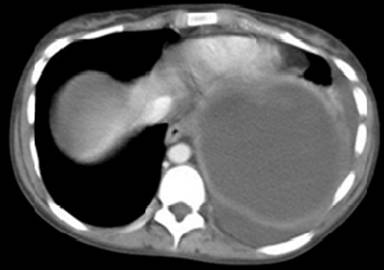

The next patient was a 23-year-old woman with a history of alcohol and opiate dependency who was admitted with increasing left upper quadrant pain for two weeks on a background of epigastric discomfort for three months. She was haemodynamically stable, serum amylase was 335 U/L, and white cell count was 14.2 x109/L. A CT scan of her abdomen showed a large pseudocyst in the area of the tail of the pancreas and spleen as shown in Figure 3.

Figure 3. Large pseudocyst in splenic area (Case #2). |